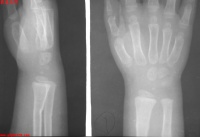

青枝骨折

青枝骨折多见于儿童,“青枝”两个是借用来的,在植物的青嫩枝条中,常常会见到折而不断的情况。儿童的骨骼中含有较多的有机物,外面包裹的骨外膜由特别的厚,因此在力学上就具有很好的弹性和韧性,不容易折断,遭受暴力发生骨折就会出现与植物青枝一样折而不断的情况,骨科医生就把这种特殊的骨折称之为青枝骨折。